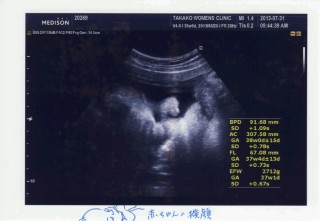

2848gの大きめな男の子です(^^) 子宮口も指一本分開いてて、赤ちゃんも下がってきてて、弱い張りがちょこちょこあるので早ければ37週で産まれると先生に言われました。 37週の健診で3000gいっちゃうと言ってました。

2708gの男の子です!頭は小さめとのことです。